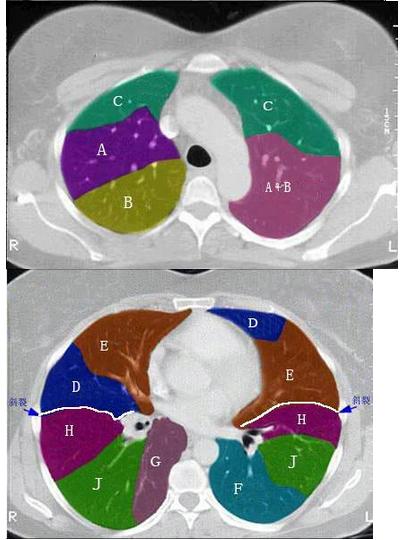

右肺下叶基底段位置图

右肺下叶基底段位置图,右肺下叶前基底段

s7:内基底段,s8:前基底段,s9:外基底段,s10:后基底段】 左肺 上叶

结合肺段模式图,选出右肺下叶的组成()

结合肺段模式图,右肺下叶的组成是()

肺段划分

肺的分叶和分段详细图